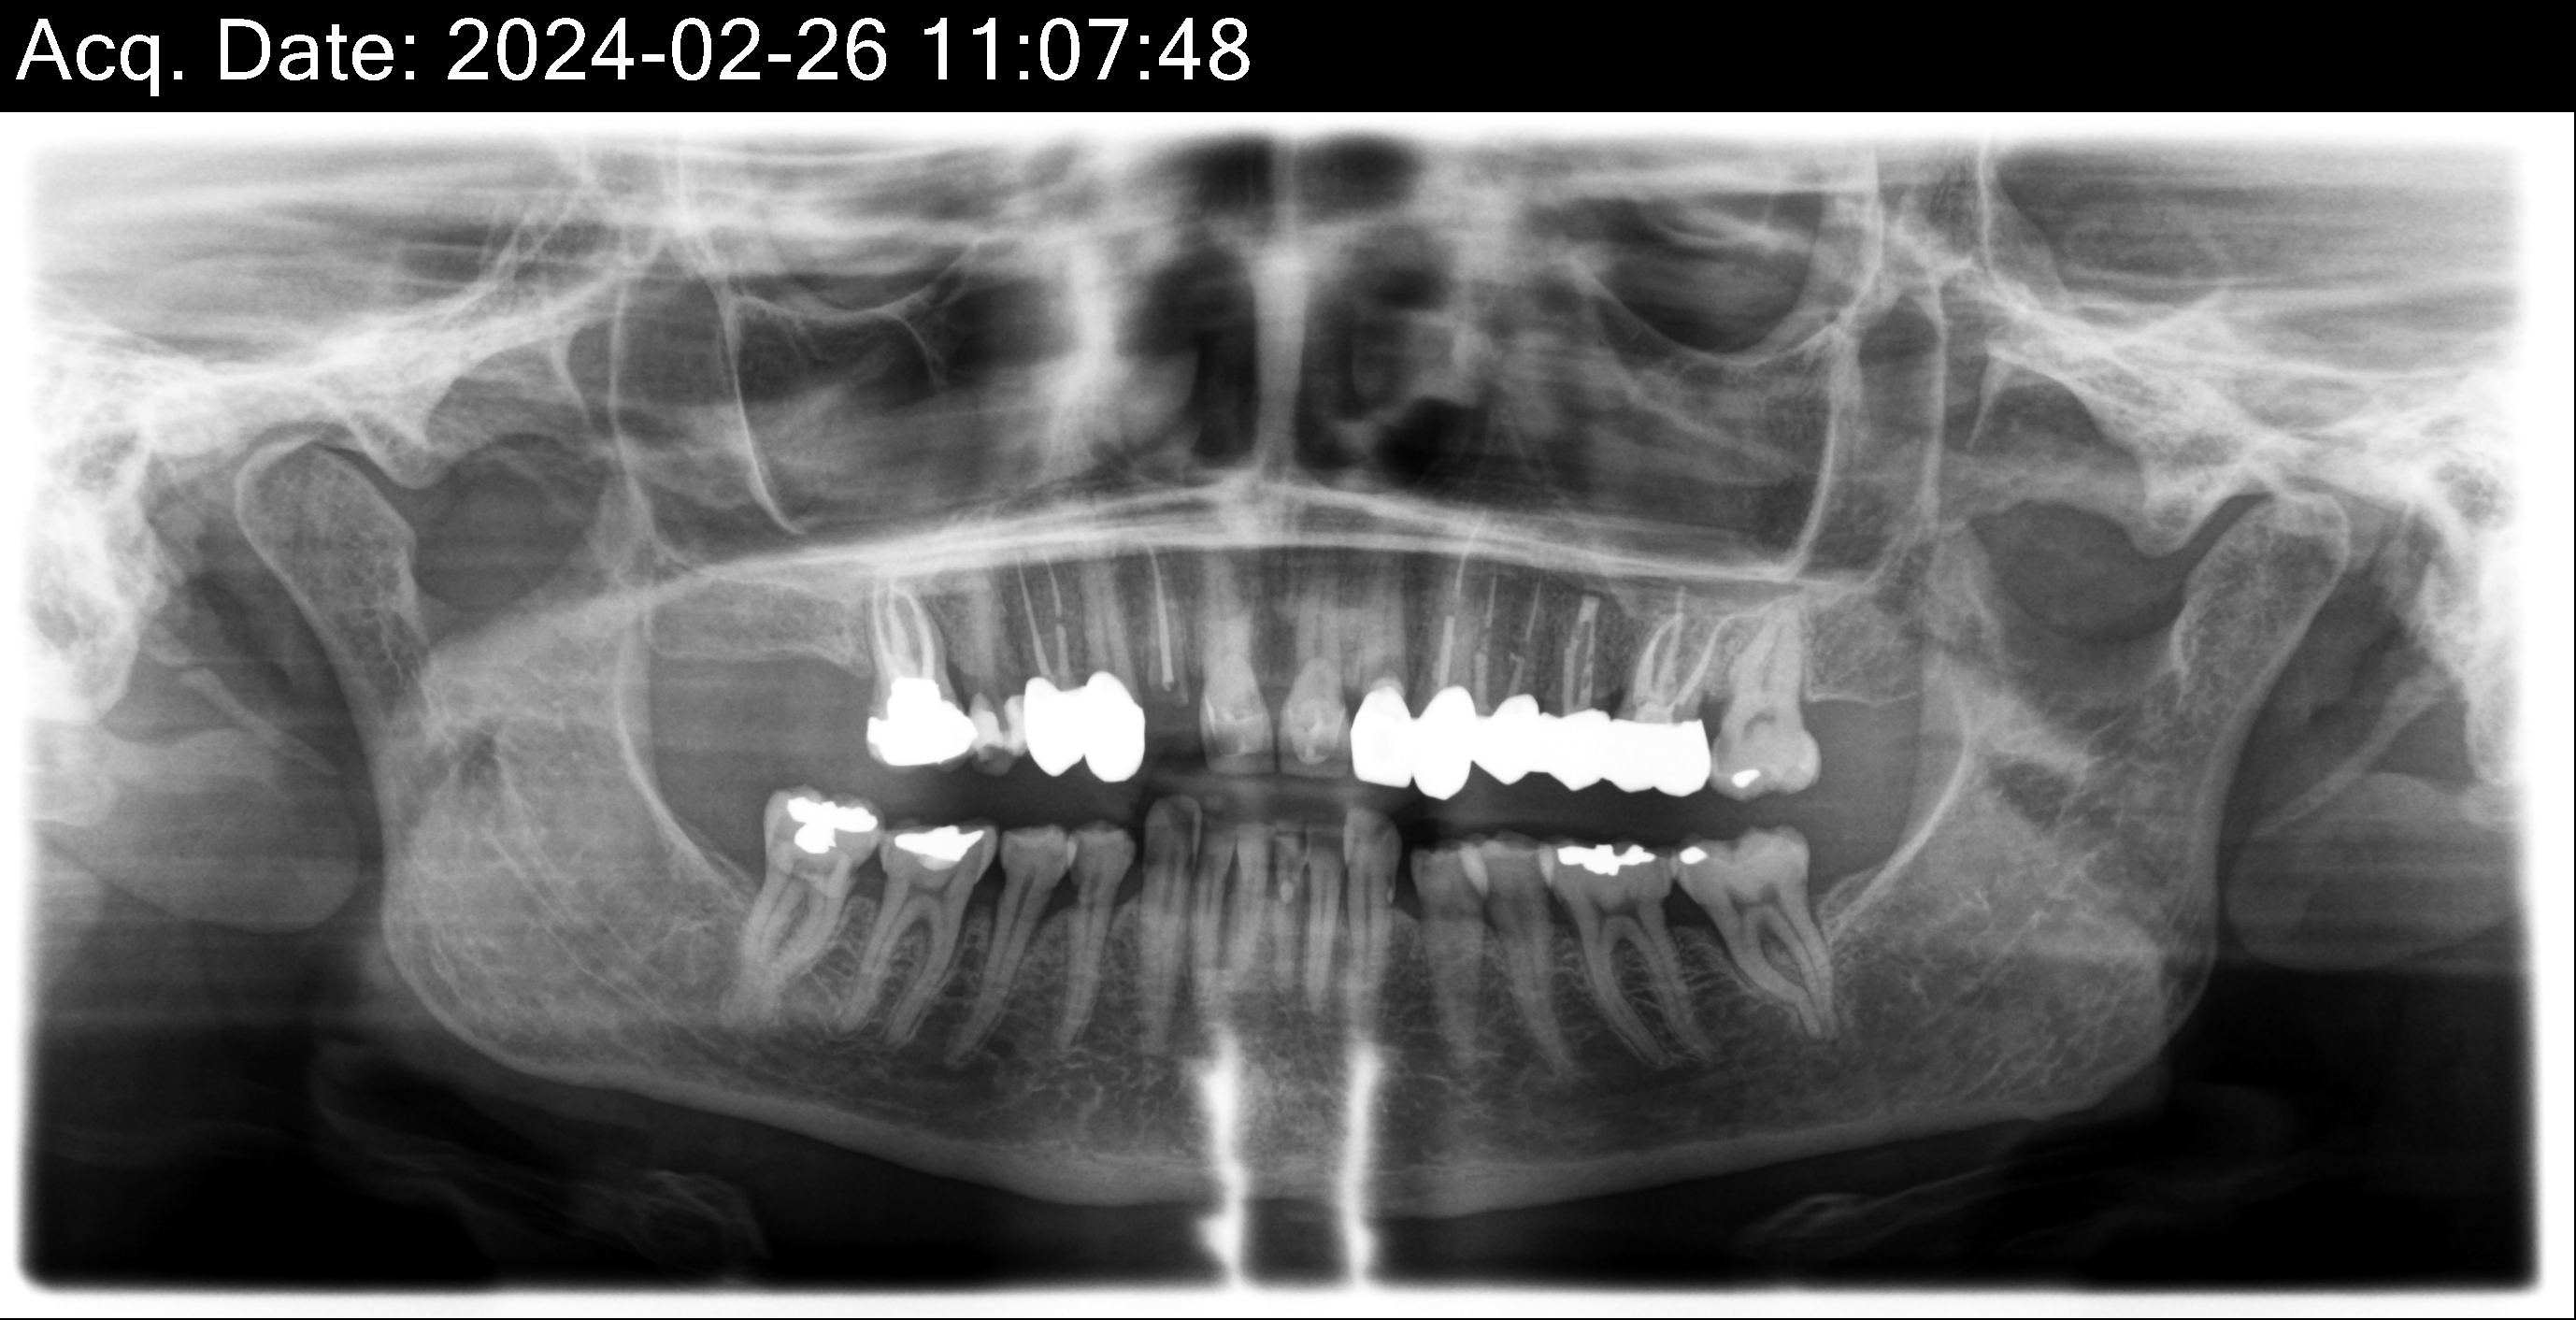

Dental Auction No. 11561: Several extractions and All-on-4 Top and bottom arches

12,13,14 have had root canals in past and now have quite a bit movement. 2-5 have all had root canals in past and now the crowns are breaking down.

Overall, all of my gums have receded and most of the bottom teeth are exposed w/ some roots and there are many cavities.